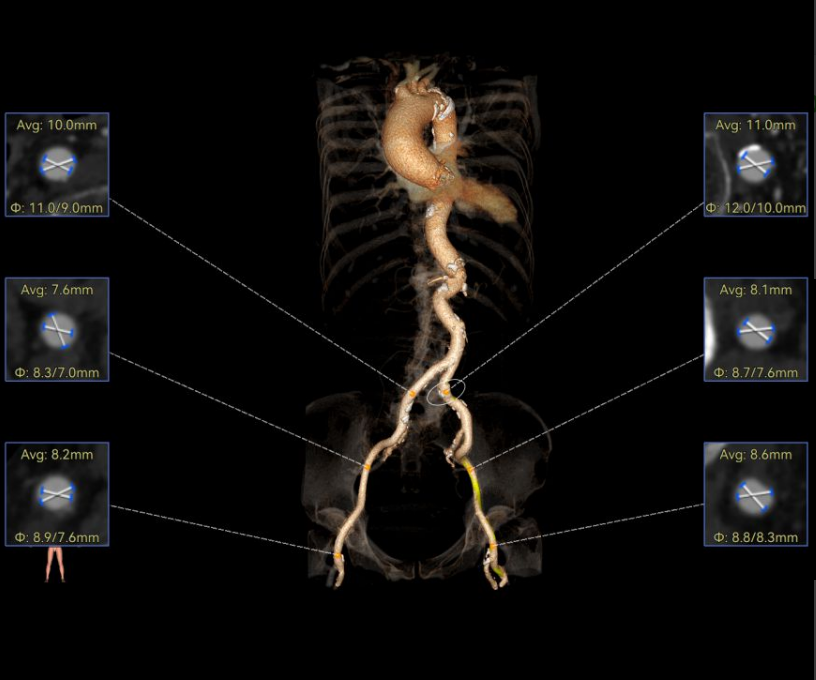

刘煜昊教授 阜外华中心血管病医院(点击查看专家详细简历) 首瓣选耐久,干瓣护航全生命周期管理 2025年ESC专家共识里指出:“推荐第一个瓣膜要选经证实具有长期耐用性的外科瓣膜与经导管瓣膜,以降低再次介入治疗的可能性 ,对于瓣环较小、根据预测有效瓣口面积(EOA)评估存在严重 PPM 风险的患者,可采用主动脉根部扩大术联合 SAVR,或植入环上瓣,对于小瓣环患者自展瓣拥有比较好的血流动力学优势”。 每一次术前评估,都是我们与患者携手面对未知的起点。我们始终以患者全生命周期获益为核心,在瓣膜选择与术式规划中,不只着眼于当下解剖适配,综合评估解剖条件、预期寿命与生活质量。从年轻患者到高龄人群,瓣膜耐久性与血流动力学稳定性始终是决策核心! 陈同峰教授 阜外华中心血管病医院(点击查看专家详细简历) 医学的进步正不断拓宽生命的边界,每一次术前评估都是对生命尊严的深度凝视,技术与人文的交融,让风险不再仅是数字的堆叠,而是成为医者与患者共同面对未知的勇气见证。术中瓣膜释放结束,到了导管测压的时候,我惊喜:瓣膜不错啊,压差为0,这不仅仅得益于瓣膜形态的设计,更是环上瓣及瓣叶材质优质的体现,感受到了 Prostyle A瓣膜在血流动力学上的卓越表现,其采用的抗钙化处理技术有效延长了瓣膜的耐久性,为患者长期生存提供了更可靠的保障。 患者病史 主诉:心慌半月; 门急诊诊断:心悸,冠状动脉粥样硬化性心脏病,心脏瓣膜病,主动脉瓣狭窄,高血压,甲状腺术后; 现病史:半月前无明显诱因出现心慌,呈间断性,伴心悸、出汗,伴头晕,无咳嗽、咳痰,无恶心、呕吐,无双下肢水肿,无放射痛及意识障碍,休息约几分钟后可自行缓解,症状反复发作,遂来我院就诊。 术前超声提示:室间隔增厚;主动脉瓣退行性变并重度狭窄;升主动脉明显增宽;室间隔增厚。 术前CT 三叶瓣,轻度钙化集中在无窦和左窦瓣叶边缘,主动脉根部直径19.3mm,LVOT直径17.7mm,LVOT向下收窄; 窦部正常,VTC空间足够,冠脉风险低; 左室腔小,收缩末径20-25mm,“自杀左室”,循环崩溃风险高;主动脉瓣环水平夹角71.1°,横位心,过弓和跨瓣存在一定困难,备snare。 外周双侧入路内径可,双侧入路能够支持20F大鞘通过,右股低分叉。 手术策略 推荐右侧股动脉为主入路,左侧为辅助入路,右股分叉上方1cm穿刺;推荐选择AV23瓣膜,18mm球囊预扩,左右重叠位:LAO 7° CAU 35°;左冠切线位:LAO 27° CRA 16°;右窦居中位:LAO 18° CAU 9°;备Snare,建议ECMO/CPB湿备,术前术中积极补液,警惕循环崩溃风险。 手术过程 在右股动脉穿刺建立通路后,顺利送入大鞘,经食道超声及血管造影确认路径稳定。18mm球囊预扩过程中,患者血压一度下降,迅速完成扩张并立即植入AV23 ProStyle A®瓣膜。瓣膜精准释放于目标位置,超声显示无明显反流及瓣周漏,血流动力学即刻改善。 主动脉根部造影 18mm球囊预扩少量反流 输送系统柔顺跨瓣 精准定位 平稳释放 80%工作位观索位置合适 释放后导管测压,压差由术前53mmHg降为0mmHg 最终造影瓣膜位置形态良好,冠脉灌注良好,无明显瓣周漏 ProStyle A®预装干瓣——助力临床最优化解决方案: 轻松过弓,精准可控:该病例为横位心,在未使用snare的情况下,过弓和跨瓣柔顺,较细的尺寸+柔顺的输送系统通过性能得到了很好的验证; 平衡的收腰设计:该病例瓣环较小且左室腔小,AV23瓣膜的平衡收腰设计既确保了锚定安全性,又保证了EOA,有效降低了循环崩溃风险,而术后0mmHg的压差的表现更加证明了优秀的血流动力学,提高了瓣膜的耐久性; 预装干瓣 便捷顺安:金仕生物专利抗钙化技术运用纳米技术去除组织内的细胞碎片和磷脂,封闭游离醛基,从根本上阻断了瓣膜钙化的多项因素,显著提升了瓣膜的耐久性;同时,相比较传统戊二醛保存方式,干式存储最大限度的保留心包的亲水亲油平衡,还原组织天然曲柔性,进一步保障了瓣叶开合,保证长期耐久性。 专家简介 王小虎 阜外华中心血管病医院(点击查看专家详细简历) 陈冲 阜外华中心血管病医院(点击查看专家详细简历) 赵一品 阜外华中心血管病医院(点击查看专家详细简历)